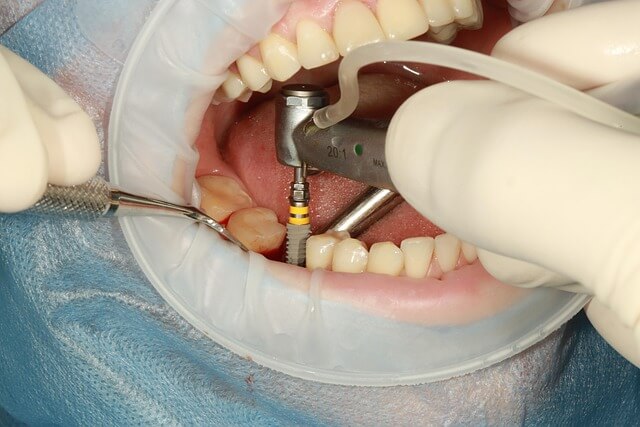

부정교합이 심하면 턱의 위치 자체가 틀어진 경우가 있습니다. 이때는 단순 교정으로 해결되지 않아 복합 치료가 필요해요. 하지만 무조건 큰 시술로 가기보다 정확한 진단이 우선입니다. 처음 진단받을 때 찍은 3D CT 영상 덕분에 제 문제는 ‘심각한 턱 틀어짐이 아님’을 알 수 있었죠. 그래서 단계별 치료를 선택했습니다. 부정교합 상태라도 정밀 검사를 통해 가장 덜 부담스러운 접근이 가능합니다.